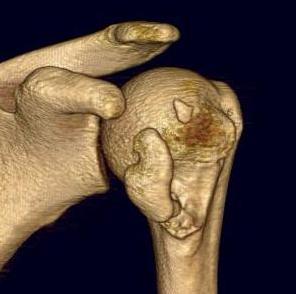

CT

LTLT

Lesser tuberosity can become overgrown